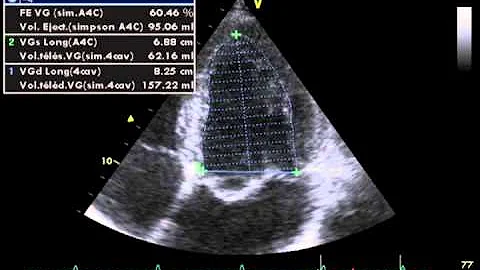

Ejection Fraction Measurement

Simpson's method for EF measurement by Simpson's method BY: Seyed A Sadatian MD. RDCS, RDMS. RVT.